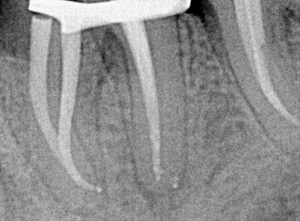

Сколько времени потратили в первое посещение на работу с шестым зубом не столь важно. Доктор, может быть, основную часть работы оставил на повторный визит. Главное, что бы после пломбирования корневых каналов он выглядел на снимке примерно так.